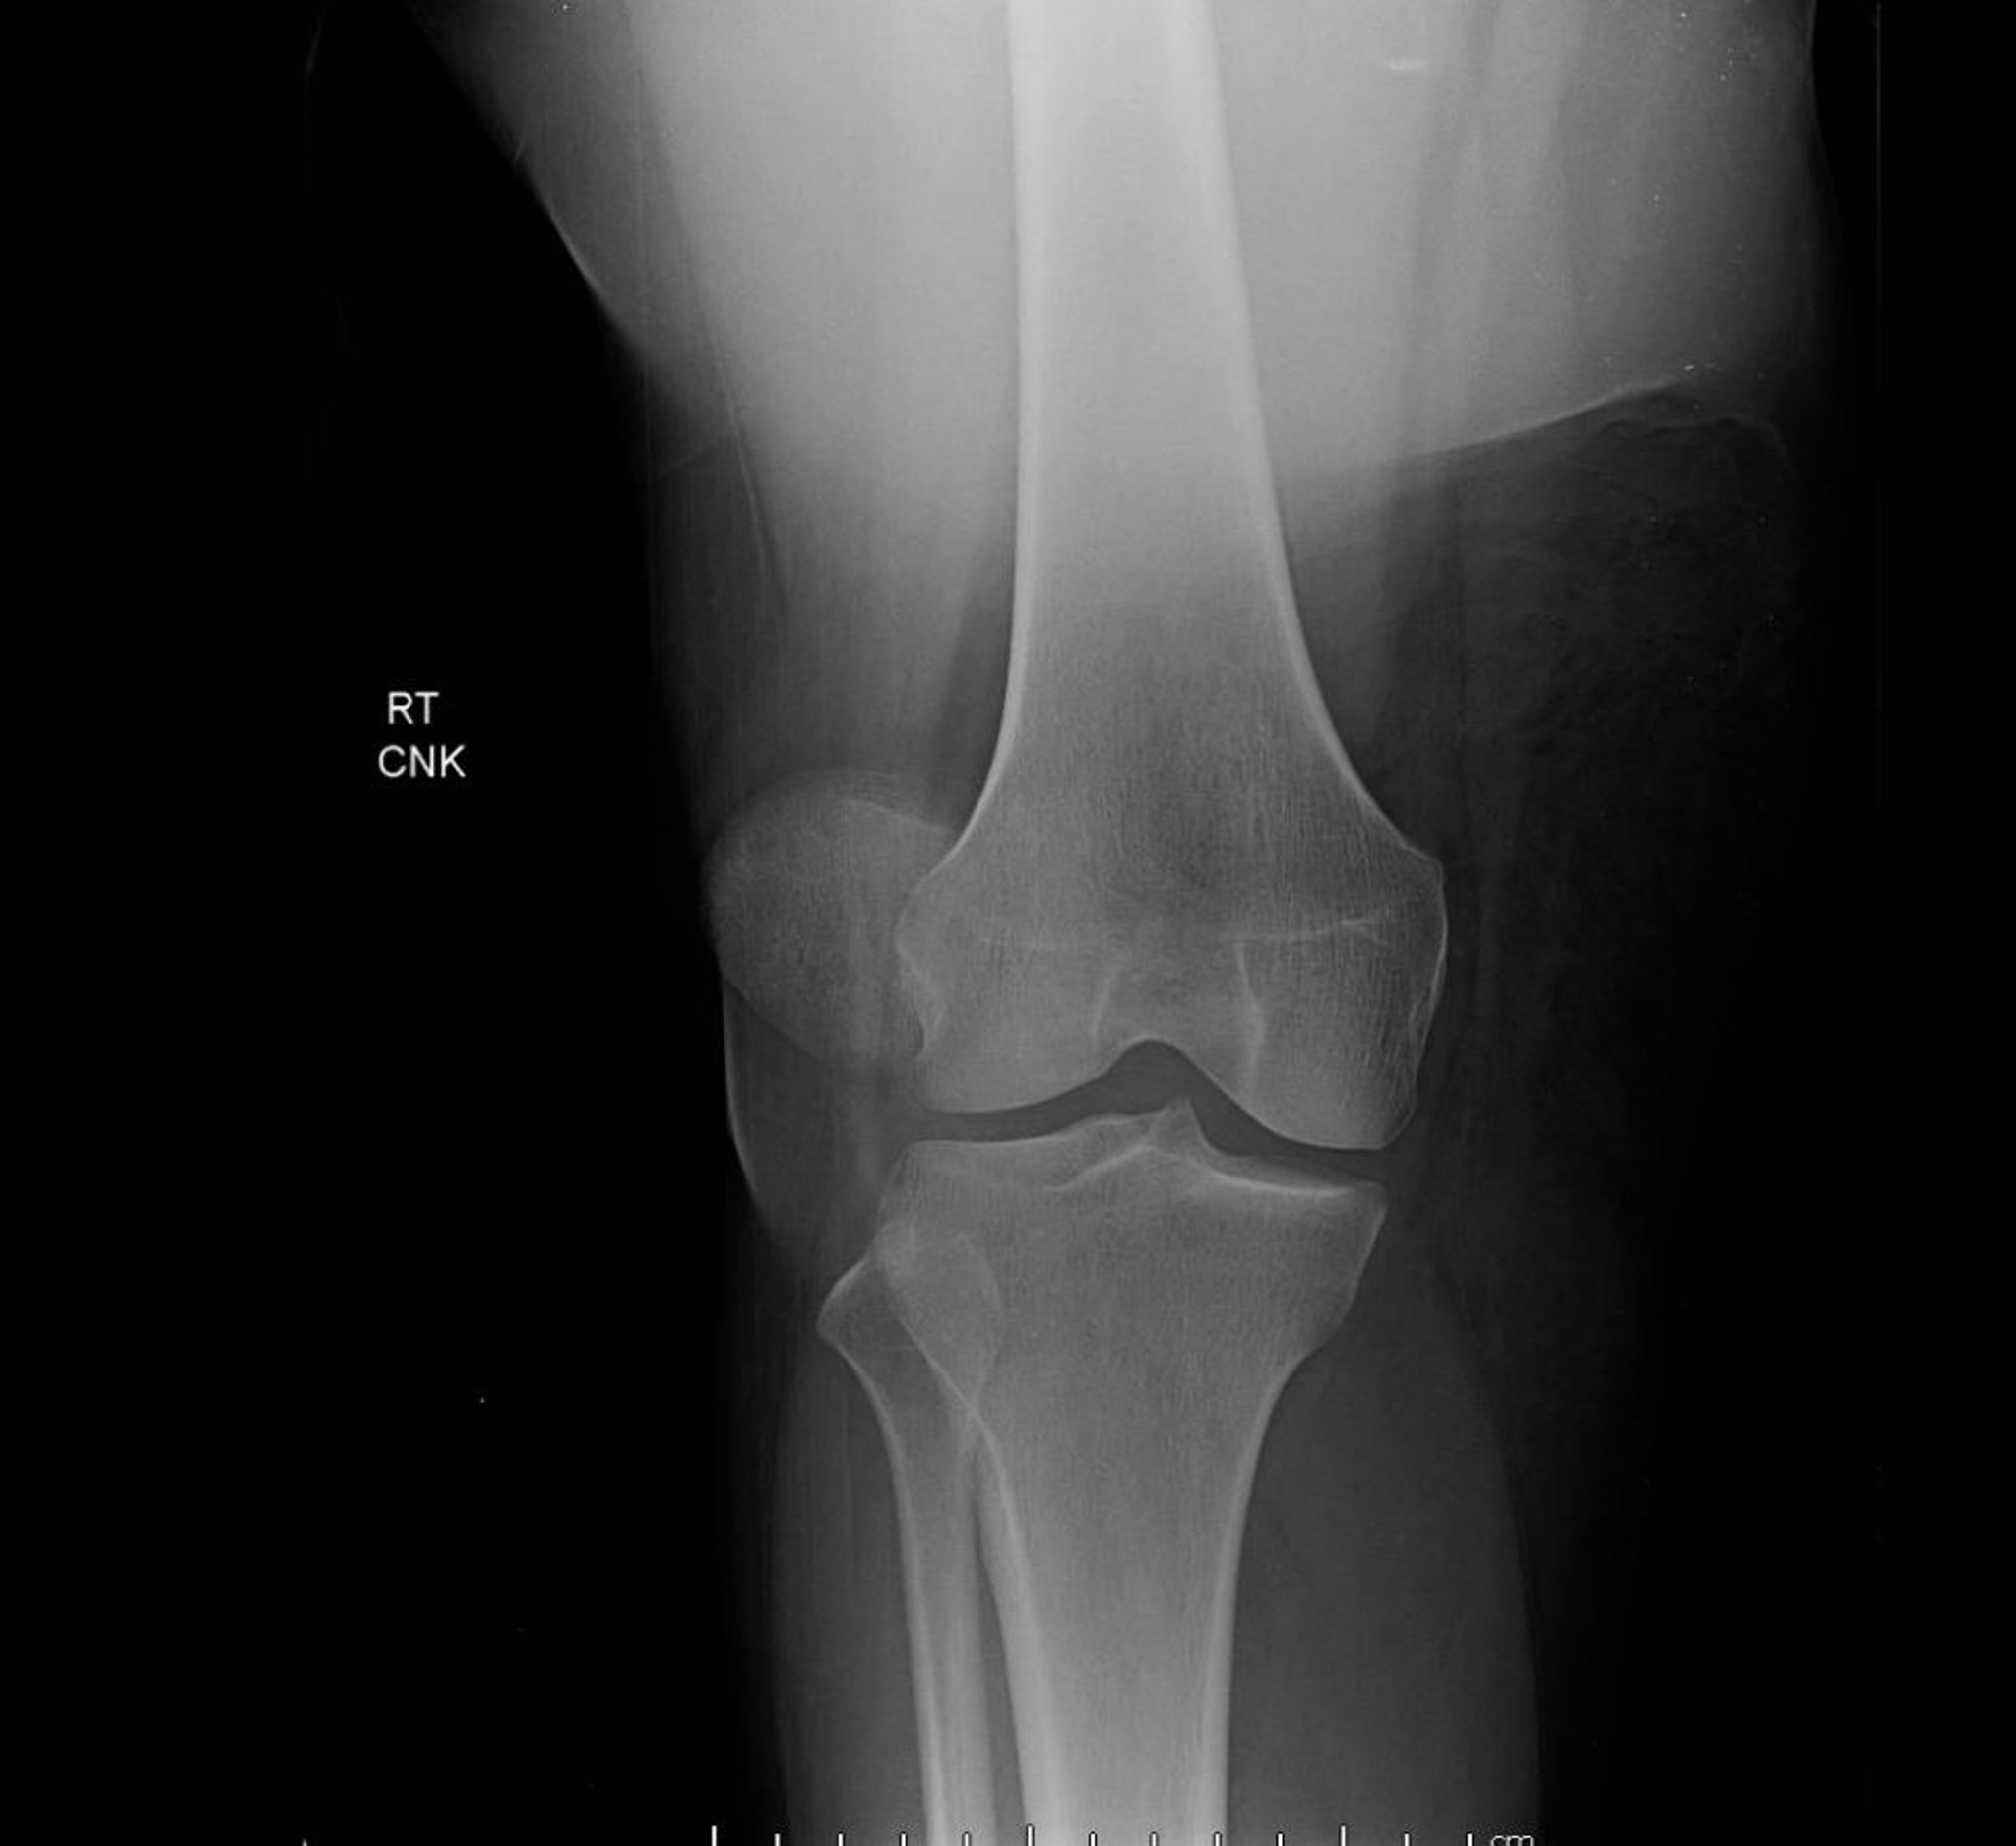

Trật khớp xương bánh chè (X-quang)

Hình ảnh trước-sau của khớp gối cho thấy trật xương bánh chè, đặc trưng bởi sự dịch chuyển sang bên mức độ nhiều của xương bánh chè, bên ngoài vị trí bình thường của nó giữa các lồi cầu xương đùi.

Hình ảnh do bác sĩ Danielle Campagne cung cấp.